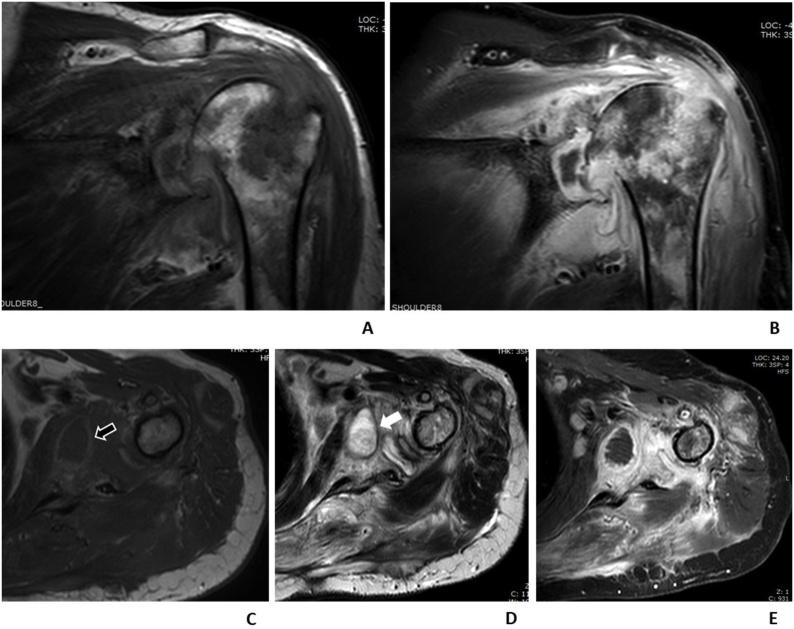

Of the 136 pyomyositis patients, 71 (52.2 %) patients had bacterial pyomyositis while 65 (47.8 %) patients had tuberculous pyomyositis. Seventy-seven patients (56.6 %) had intramuscular abscess. On multivariable analysis, bacterial pyomyositis was associated with diabetes mellitus (odds ratio [OR] 3.17, 95 % confidence interval [CI] 1.30-8.24) and bone marrow involvement (OR 5.02, 95 % CI 1.21-34.4). Spinal involvement had a significantly lower likelihood of bacterial pyomyositis (OR 0.25, 95 %CI 0.11-0.54). In patients with intramuscular abscess, diabetes mellitus and hyperintense on T2-weighted images at the abscess wall had a significantly higher likelihood of bacterial pyomyositis (OR 5.21, 95 %CI 1.33-25.42 and OR 5.34, 95 %CI 1.36-24.71, respectively), whereas spinal involvement had a significantly lower likelihood of bacterial pyomyositis (OR 0.09, 95 %CI 0.02-0.30).

Magnetic resonance imaging has modest accuracy for differentiation of tuberculous and bacterial pyomyositis. Diabetes mellitus and extraspinal pyomyositis were the predictors of bacterial pyomyositis. Presence of T2 hyperintense wall of intramuscular abscess was also the predictor of bacterial pyomyositis.

在136例脓性肌炎患者中,71例(52.2%)为细菌性脓性肌炎,65例(47.8%)为结核性脓性肌炎。77例(56.6%)患者有肌肉内脓肿。多变量分析显示,细菌性脓性肌炎与糖尿病(比值比[OR] 3.17,95%置信区间[CI] 1.30 - 8.24)及骨髓受累(OR 5.02,95% CI 1.21 - 34.4)相关。脊柱受累的患者患细菌性脓性肌炎的可能性显著降低(OR 0.25,95% CI 0.11 - 0.54)。在有肌肉内脓肿的患者中,糖尿病及脓肿壁在T2加权图像上呈高信号的患者患细菌性脓性肌炎的可能性显著更高(分别为OR 5.21,95% CI 1.33 - 25.42和OR 5.34,95% CI 1.36 - 24.71),而脊柱受累的患者患细菌性脓性肌炎的可能性显著降低(OR 0.09,95% CI 0.02 - 0.30)。

磁共振成像对结核性和细菌性脓性肌炎的鉴别准确性一般。糖尿病和脊柱外脓性肌炎是细菌性脓性肌炎的预测因素。肌肉内脓肿壁T2高信号也是细菌性脓性肌炎的预测因素。